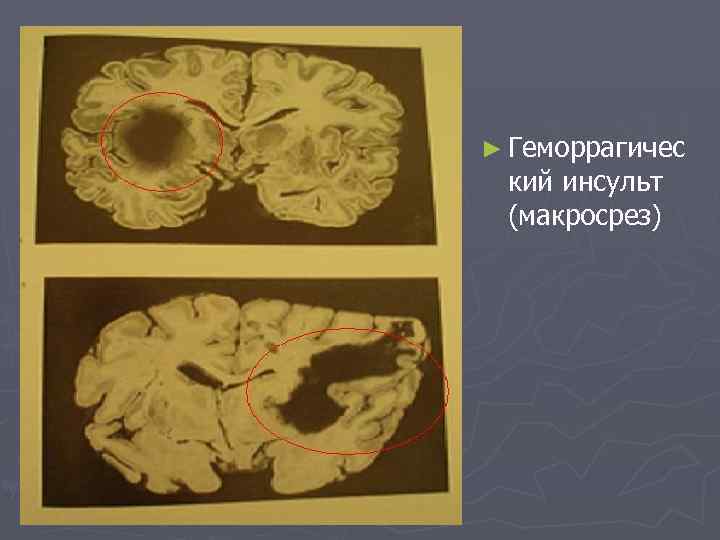

► Геморрагичес кий инсульт (макросрез)